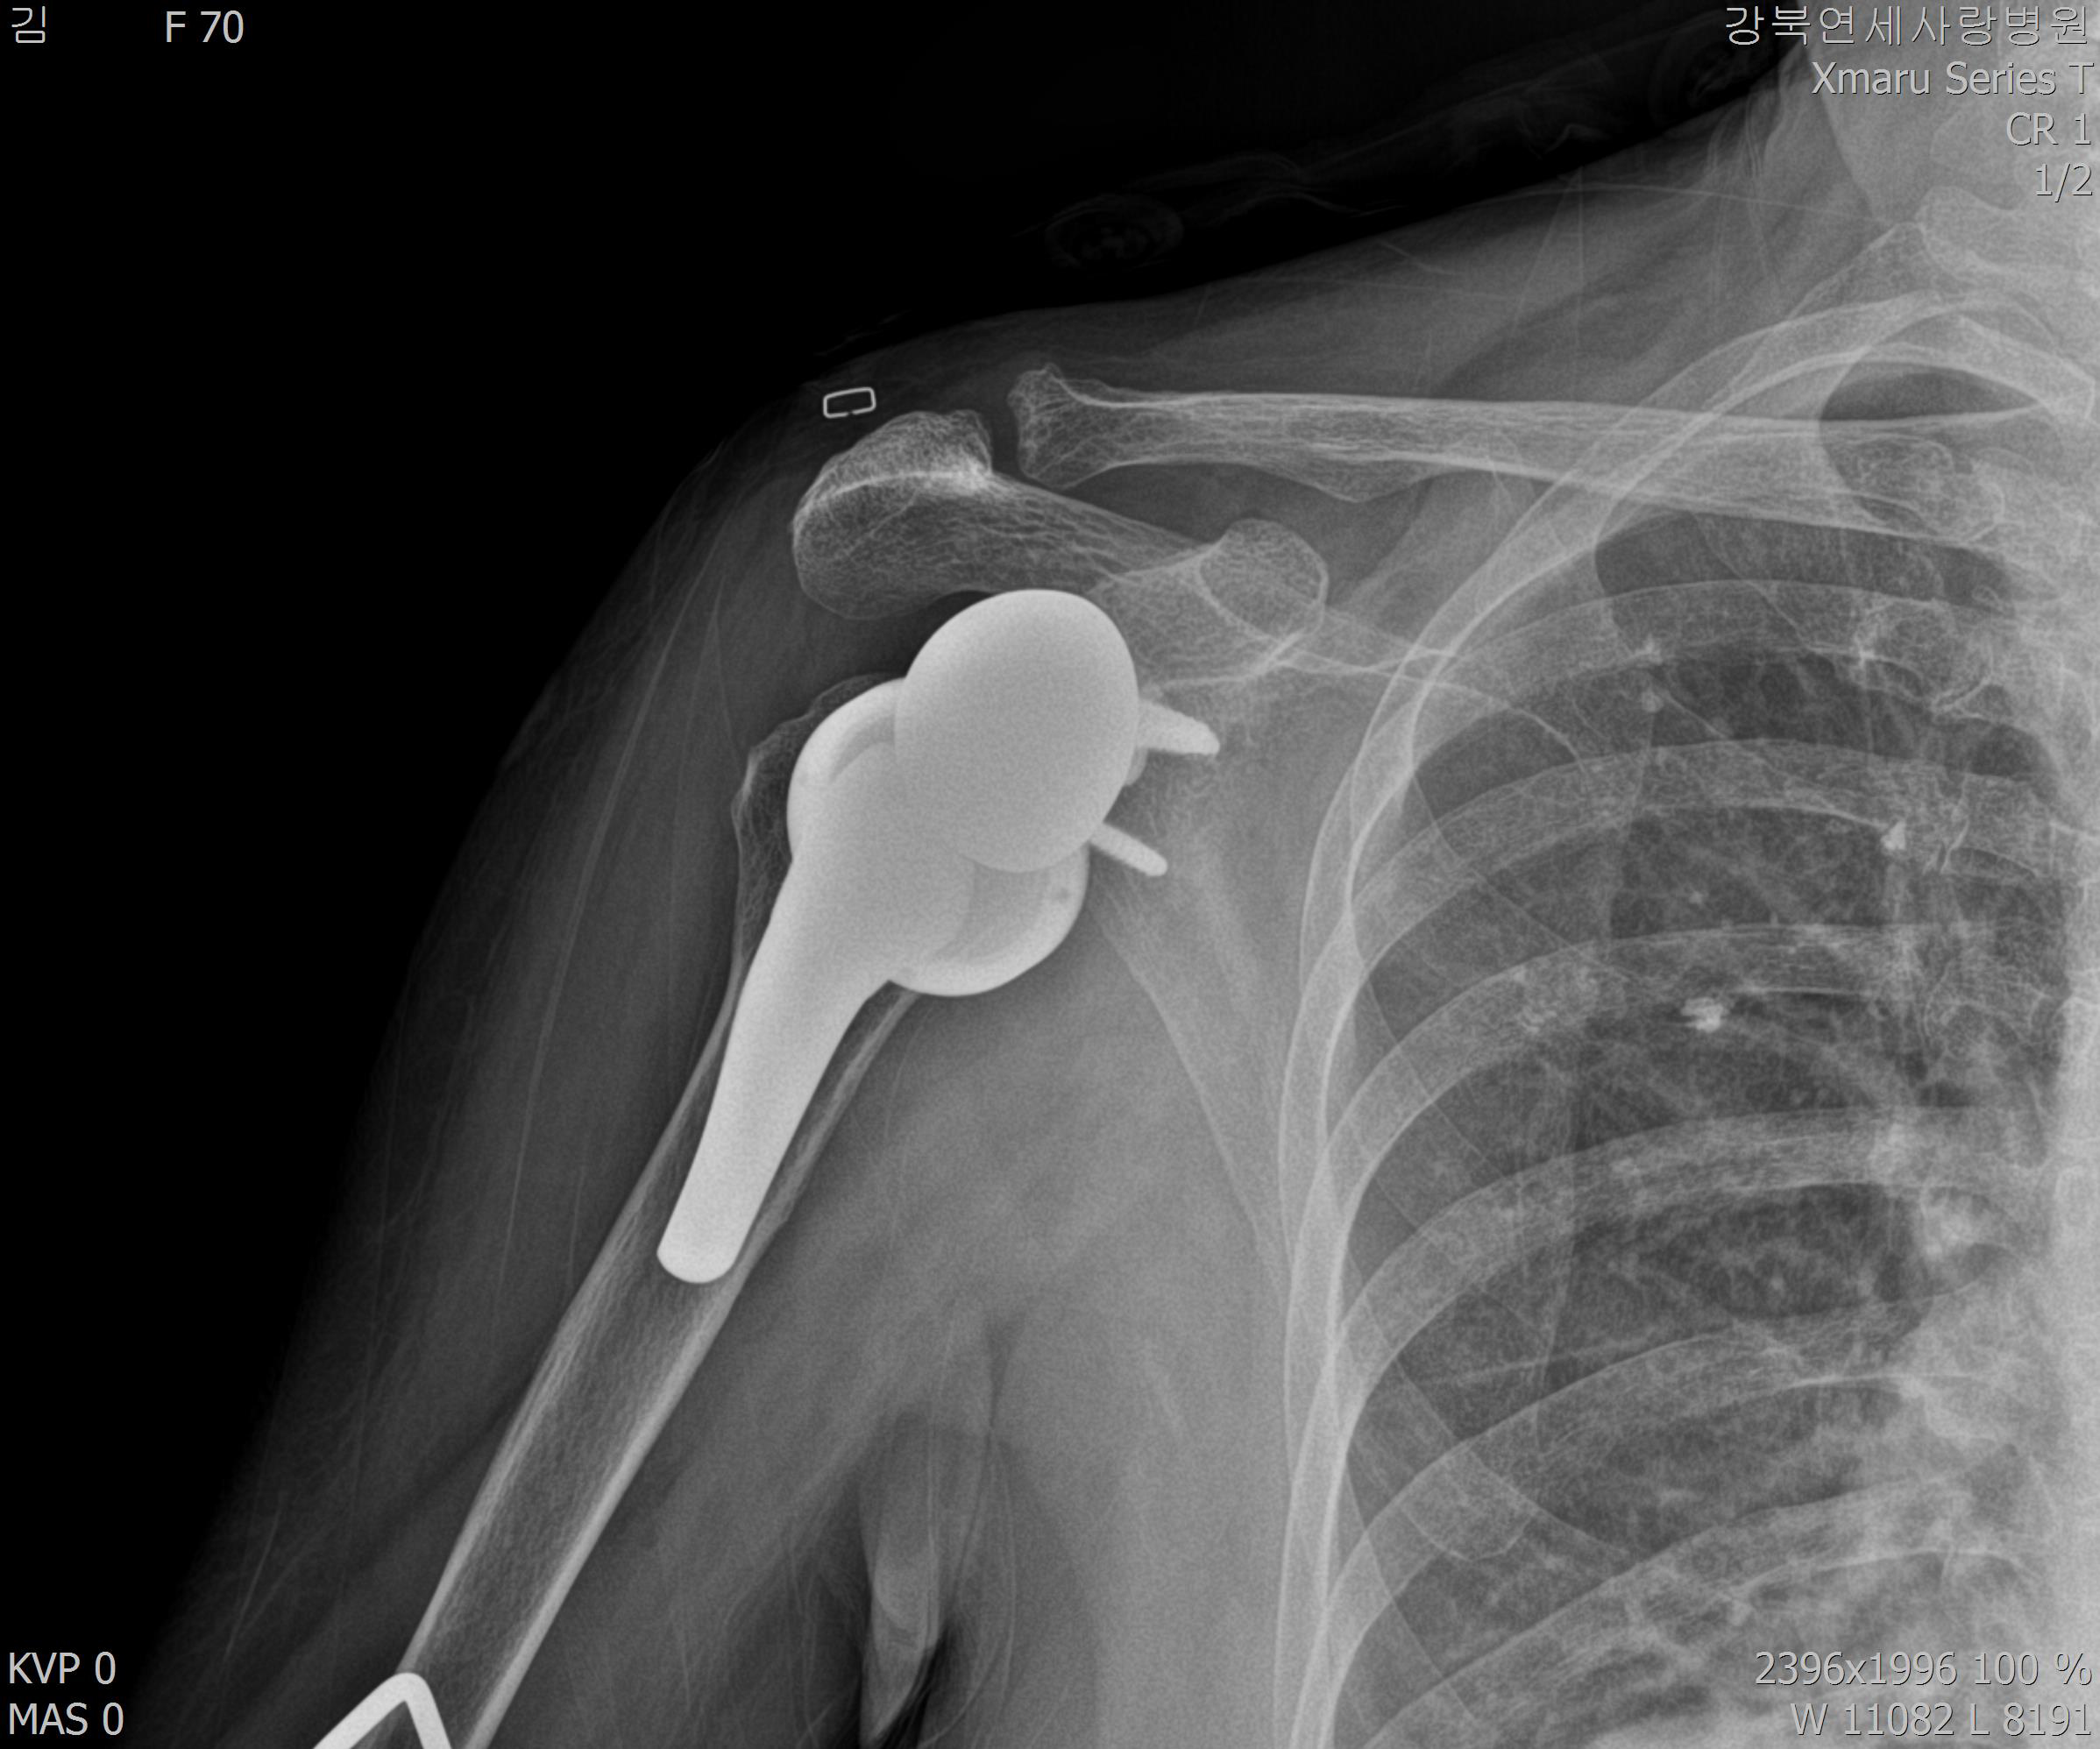

| 어깨 인공관절로 치료한다 | |||||